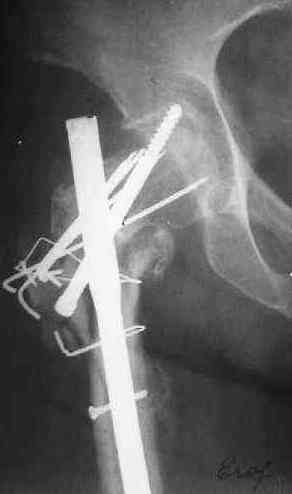

Подвертельное несращение

Поступила женщина 62 лет. В X 2006 оперировна в одной из горбольниц, по поводу, видимо, оскольчатого подвертельного перелома.

Почему сделан такой странный остеосинтез - пока неизвевстно. 3 мес. в тазобедренной гипсовой повязке. Картина через полгода после операци, в апреле - первый снимок. После этого снимка убрали винт, проникающий в сустав. Картина на сегодня - следующие 2 снимка.

Dear All, A female 62 y.o. referred to our unit. In X 2006 was operated somewhere - open reduction and fixation of a fragmented subtrochanteric fracture. Why so strange fixation was performed - no data at the moment. 3 month in plaster cast. Image 1 - Apr 2007, 6 month after the surgery. The screw was removed some days later.

Other images present the current situation.

Wound healed uneventfully. Now there is local hyperemia at the lateral side of the proximal femur. WBC - 6.2, ESR - 48 m/h.